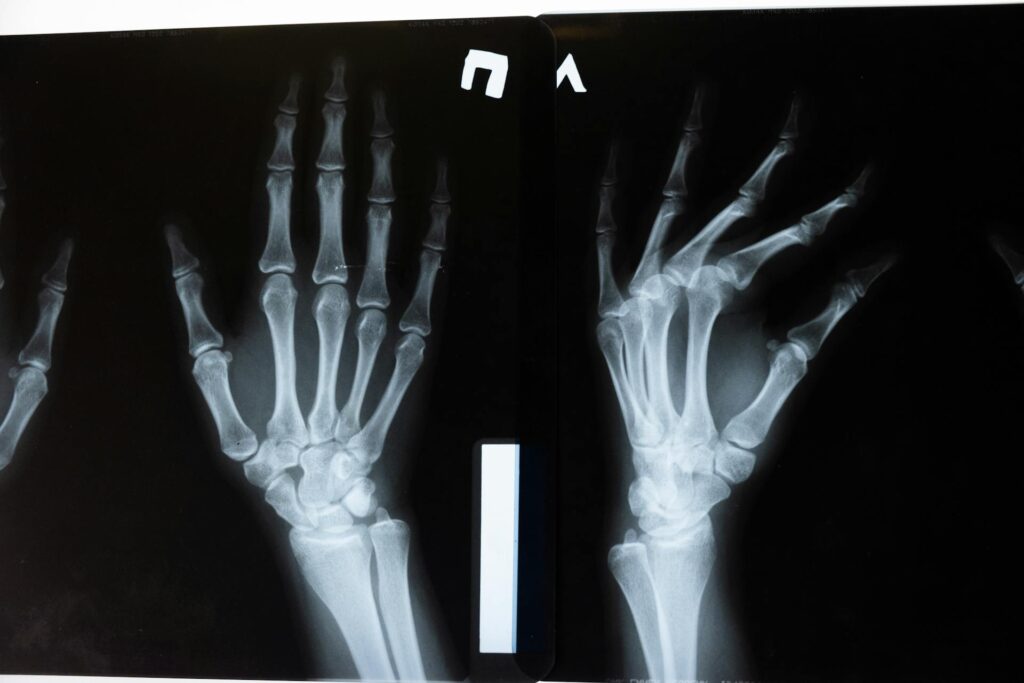

Parmi les lésions les plus souvent rencontrées dans le sport, on retrouve en premier lieu tout ce qui concerne les membres supérieurs : fracture du poignet, fracture de la clavicule, fracture des doigts…

- La fracture de la main : Si se rattraper sur les mains est un réflexe qui nous protège (notamment au visage), cela peut aussi causer des fractures, et notamment celle de la main. Mais les coups portés à mains nues et chocs peuvent aussi être en cause, ce qui explique pourquoi on retrouve cette blessure dans certains sports !

On va donc immobiliser la zone touchée si possible, et éventuellement proposer des antalgiques. Plusieurs types d’imageries peuvent être réalisés pour confirmer le diagnostic (radiographie standard, scanner ou encore IRM).